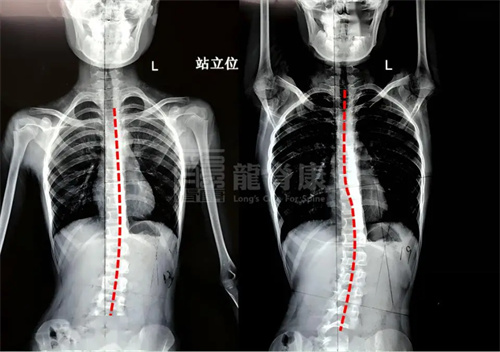

曾有一位来自河南的13岁女孩,初诊时胸椎侧弯32度。当地建议回家吊单杠。家长极度重视,甚至为孩子办理休学,在家专门安装了单杠。孩子非常刻苦,每天累计悬吊超过2小时,坚持9个月。

然而复诊时,X光片显示:她的侧弯从32度进展至44度!9个月的汗水与坚持,换来的却是畸形的明显加重。这个案例典型地说明了盲目锻炼的风险。